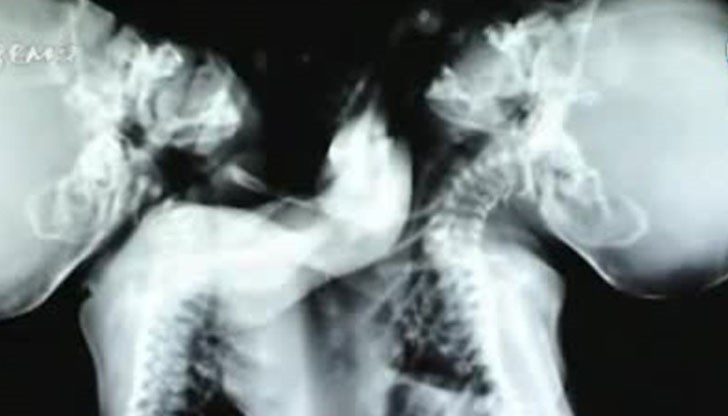

Нов пореден опит за спасяване на поне едното от двете бебета правят близките на сиамските близнаци, родени в Сливен миналата година.

Установено е, че едното бебе – Янко, непрекъснато се влошава. Въпреки мрачните прогнози другото дете – Богдан, е сравнително стабилно, обясни бабата на близнаците Мария, цитирана от Нова телевизия.

Това е трети опит на семейството да поиска от Фонда да даде шанс за живот на Богдан. До момента имат два отказа заради мнението на лекари у нас, че операцията е невъзможна и рискува и двата живота. Въпреки това семейството на бебетата е съгласно да поеме риска.

От медицински университети в САЩ вече изразиха мнение, че заради общите органи на децата, свързаната костна система и общото много тежко състояние, опит за разделяне на бебетата би бил фатален. През изминалите месеци малформациите при едното бебе са станали необратими, но последните епикризи ще подскажат на лекарите дали да опитат.